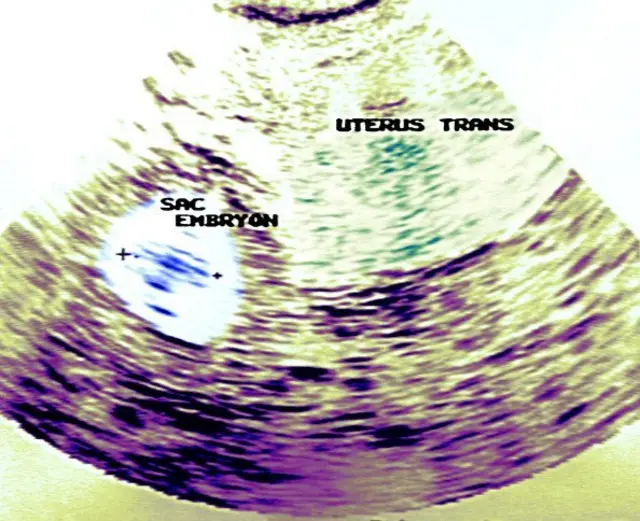

அவருடைய கருப்பைக்கு அருகில் வளையம் போன்ற ஒரு அமைப்பு இருந்தது.

ஸ்கேன் கருவிக்கு அருகே நான் சென்றேன். கருப்பைக்கு வெளியே, கரு தரித்திருந்தது.

சில நேரங்களில் கருப்பைக்குள் கரு தங்குவதில்லை. ஆனால் அருகில் உள்ள குழாயில் உருவாகிறது. அந்தக் குழாயின் அகலம் குறைவானது என்பதால், இரண்டு மாதங்களுக்கு மேல் கரு வளர முடிவதில்லை.

அதன் அளவை வர்ஷிதா சோதித்துப் பார்த்தார். ``மேடம் 4.2 சென்டிமீட்டர்கள் உள்ளது'' என்று என்னிடம் கூறினார். மிகச் சிறிய கருதான். அதில் லேசான இருதய துடிப்பு இருந்தது.

குழாயில் கரு தங்கினால், ஊசி மருந்து மூலமாக சில நேரங்களில் சிகிச்சை அளிக்கப்படும். ஆனால் அளவு 3.5 சென்டிமீட்டருக்கு மேலாக இருந்தால் அல்லது இருதய துடிப்பு உணரப்பட்டால், அறுவை சிகிச்சை மூலமாக கூடிய சீக்கிரத்தில் அதை நாம் அகற்றியாக வேண்டும். உடனடியாக அதற்கு சிகிச்சை தராவிட்டால், சில நேரங்களில் குழாயில் வெடித்துக் கொள்ளும் ஆபத்து உள்ளது.